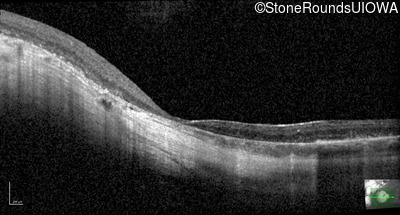

Optical Coherence Tomography - Right - 20/125

Exemplar / OCT Stack

OCT Stack